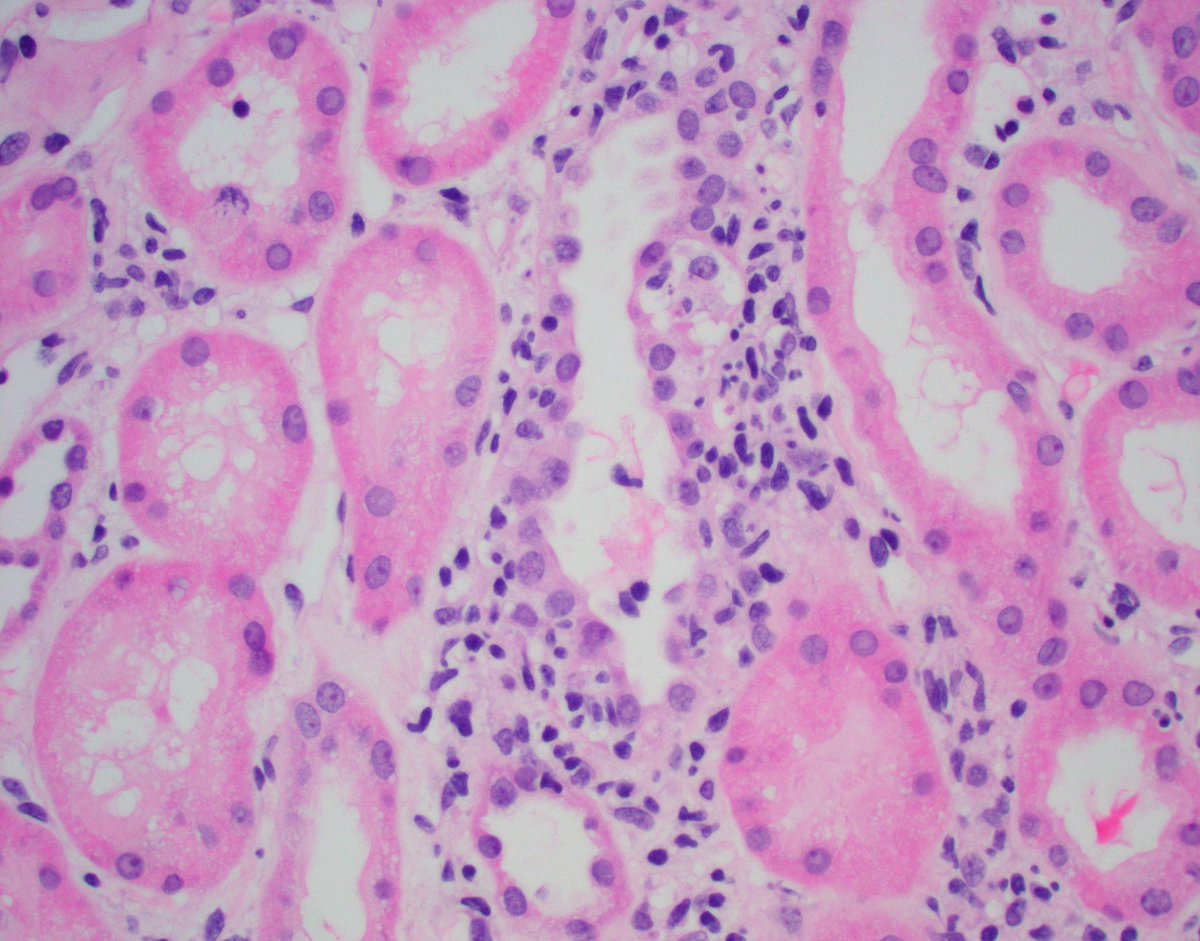

Lupus nephritis (native) : classic immune thrombi, wire loop lesions & endocapillary cells++. Extra glomerular immune deposits : C1q( PTC/TBM staining). EM: “wire-loop” & PTC immune deposits. Read our 📝 on lupus in TX. Mayo Clinic Pathology Mayo Clinic Nephrology Mayo Clinic Transplant KIReports